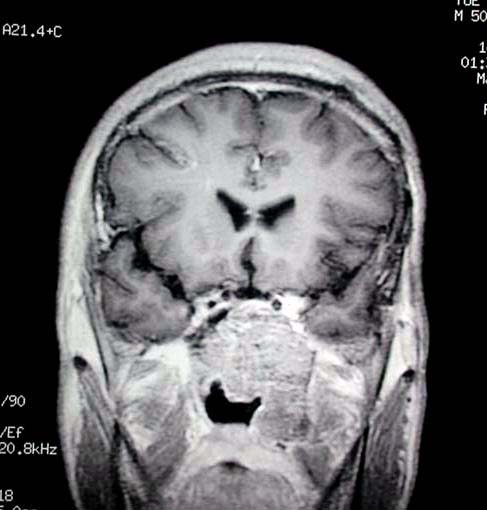

术前